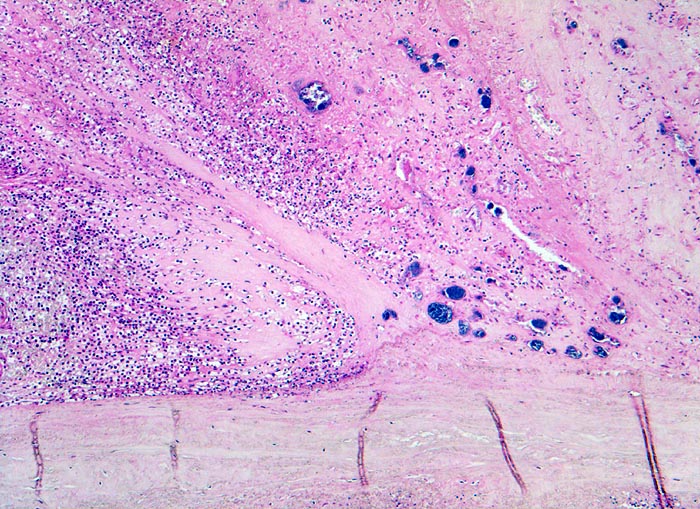

Endocarditis ulcero-polyposa der Aortenklappe

Aortenklappe

Dem fibrösen Klappengerüst aufgelagerte Klappenvegetation bestehend aus Fibrin, neutrophilen Granulozyten und herdförmig eingelagerten blauen Bakterienrasen.

Akut einsetzendes Krankheitsbild mit Fieber, Schüttelfrost, Müdigkeit und Dyspnoe. Blutkulturen wiederholt positiv für Staphylokokkus aureus. Keine Klappenvorschädigung bekannt.

Histologie

50